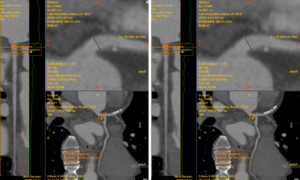

Đau ngực, mỗi cơn đau nhói kéo dài 5-10 phút, người đàn ông đến viện sàng lọc, chụp CT mạch vành 2560 lát cắt phát hiện bị hẹp mạch máu nuôi tim.